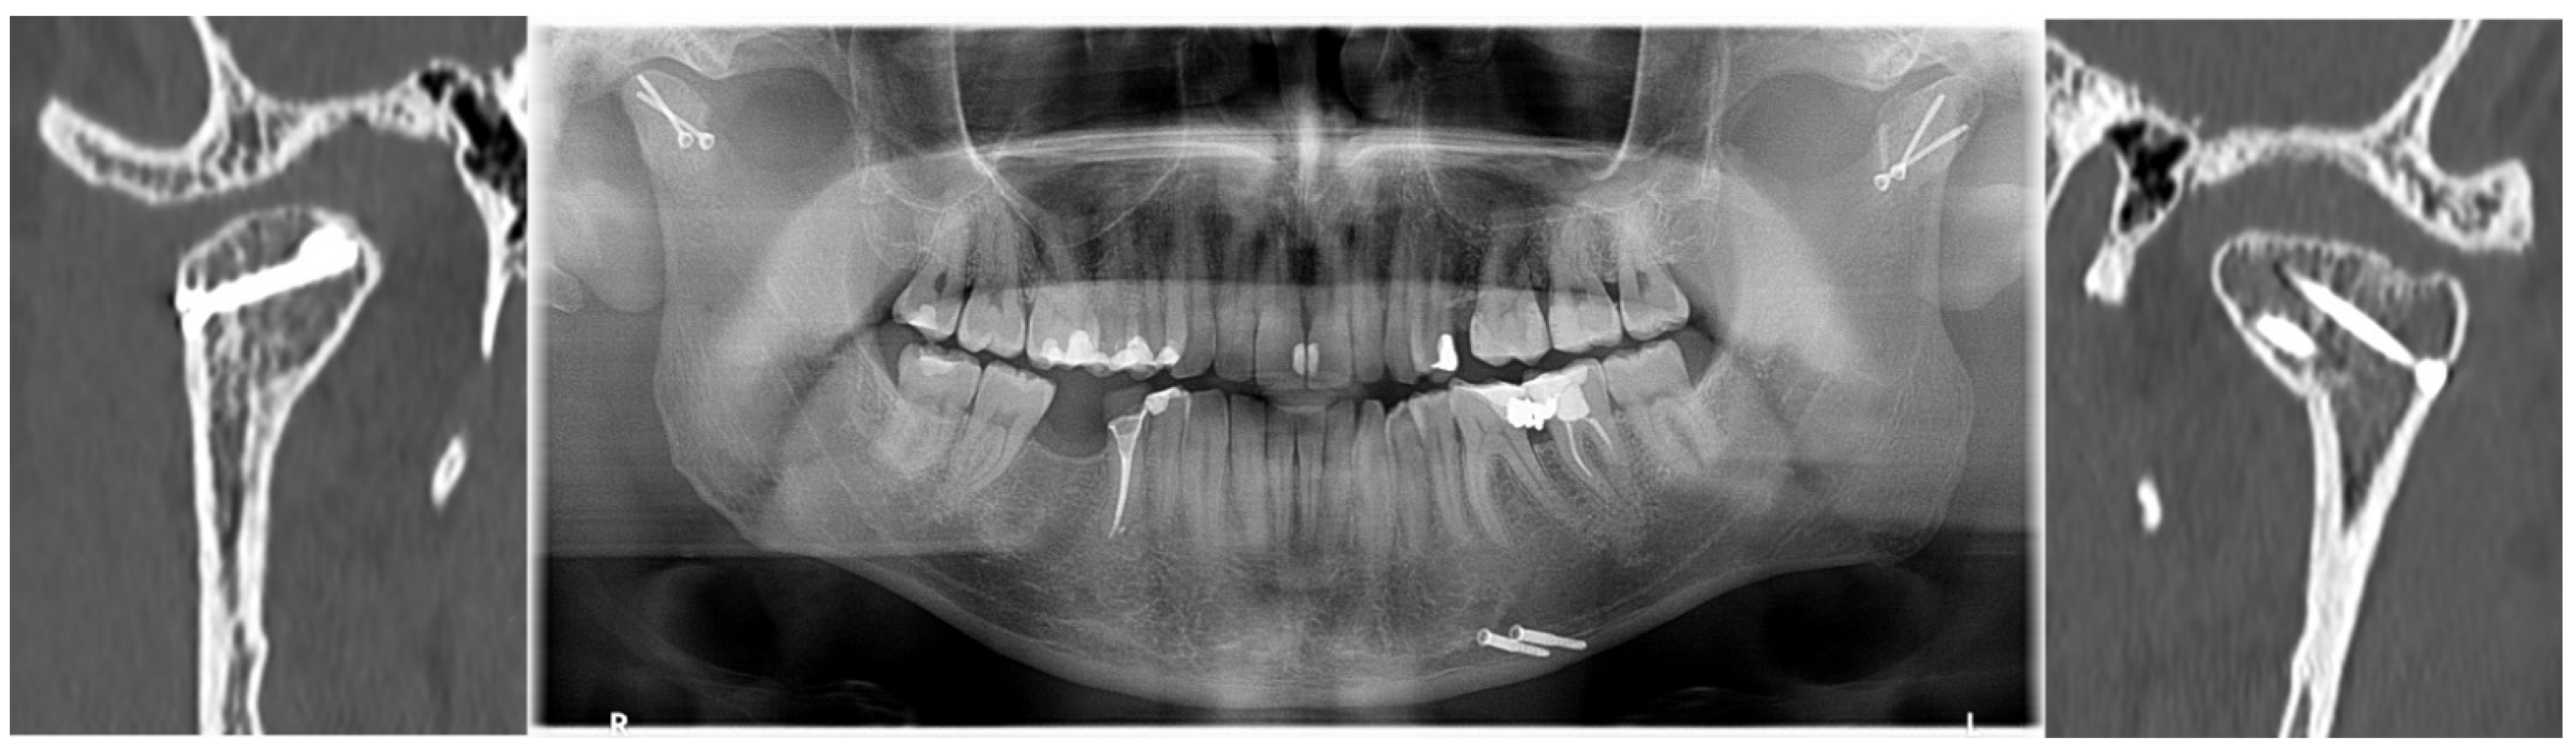

Figure 1. Radiological documentation showing the effect of surgical treatment of mandibular head fractures (examinations were acquired 12 months after osteosynthesis). A pantomogram radiograph is shown in the center as an overview study and CT coronal sections through the mandibular heads are shown on the sides. In the CT scan, the union and position of the headless compression screws can be accurately assessed (volumetric study makes it possible to obtain any cross-section). This patient had an additional fracture in the rim of the mandibular body on the left side. It was treated with lag-screws. Please note the small depression in the articular surface of the left mandibular head (CT image on the right side of this figure). It appears to be the result of a tiny shift between the fixated bone fragments. This shift, however, changes the height of the mandibular ramus.

Facial injuries are frequent trauma and most common in males (56.8–92.8%) [1,2,3,4], and the mean age ranges from 24 to 51 years [2,5]. Condylar fractures are one of the most frequent of mandibular fractures: 21–52% [6,7,8]. It appears that fractures of the mandibular head are not as rare as previously reported, e.g., the 11 fractures in 40 described condylar fractures [9]. The growing interest in surgical treatment [10,11,12,13] and free availability of computed tomography [14,15] stimulates an increase in the diagnosis of mandibular head fractures. A secondary benefit of this development is the ability to accurately monitor distant treatment outcomes in terms of the preservation of anatomical structures (Figure 1). Since the presentation by Kermer, Undt, and Rasse [16], the technique for the use of long screws in osteosynthesis of mandibular heads notes the current stage of medical development in this field.